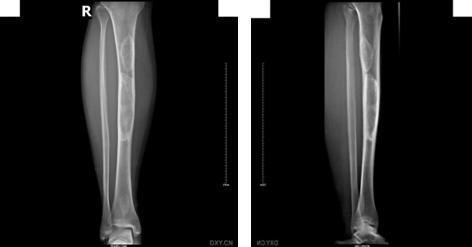

单发型病变部位在髓腔内,长管状骨的干骺端或骨干中心位或偏心位。骨皮质变薄形成缺损,呈模糊的髓腔内放射透明区,常形容为磨砂玻璃状。多发型纤维结构不良常累及数骨,同侧的髂骨、股骨、胫骨、腓骨常被累及。四肢长骨病变常累及骨的全部,髓腔宽窄不均,其增宽处骨皮质变薄并扩张。部分高度膨胀,其中有囊性改变,常表现为病理性骨折。X线表现为溶骨范围界限不清,骨皮质缺损和临近软组织肿块通常提示恶变。